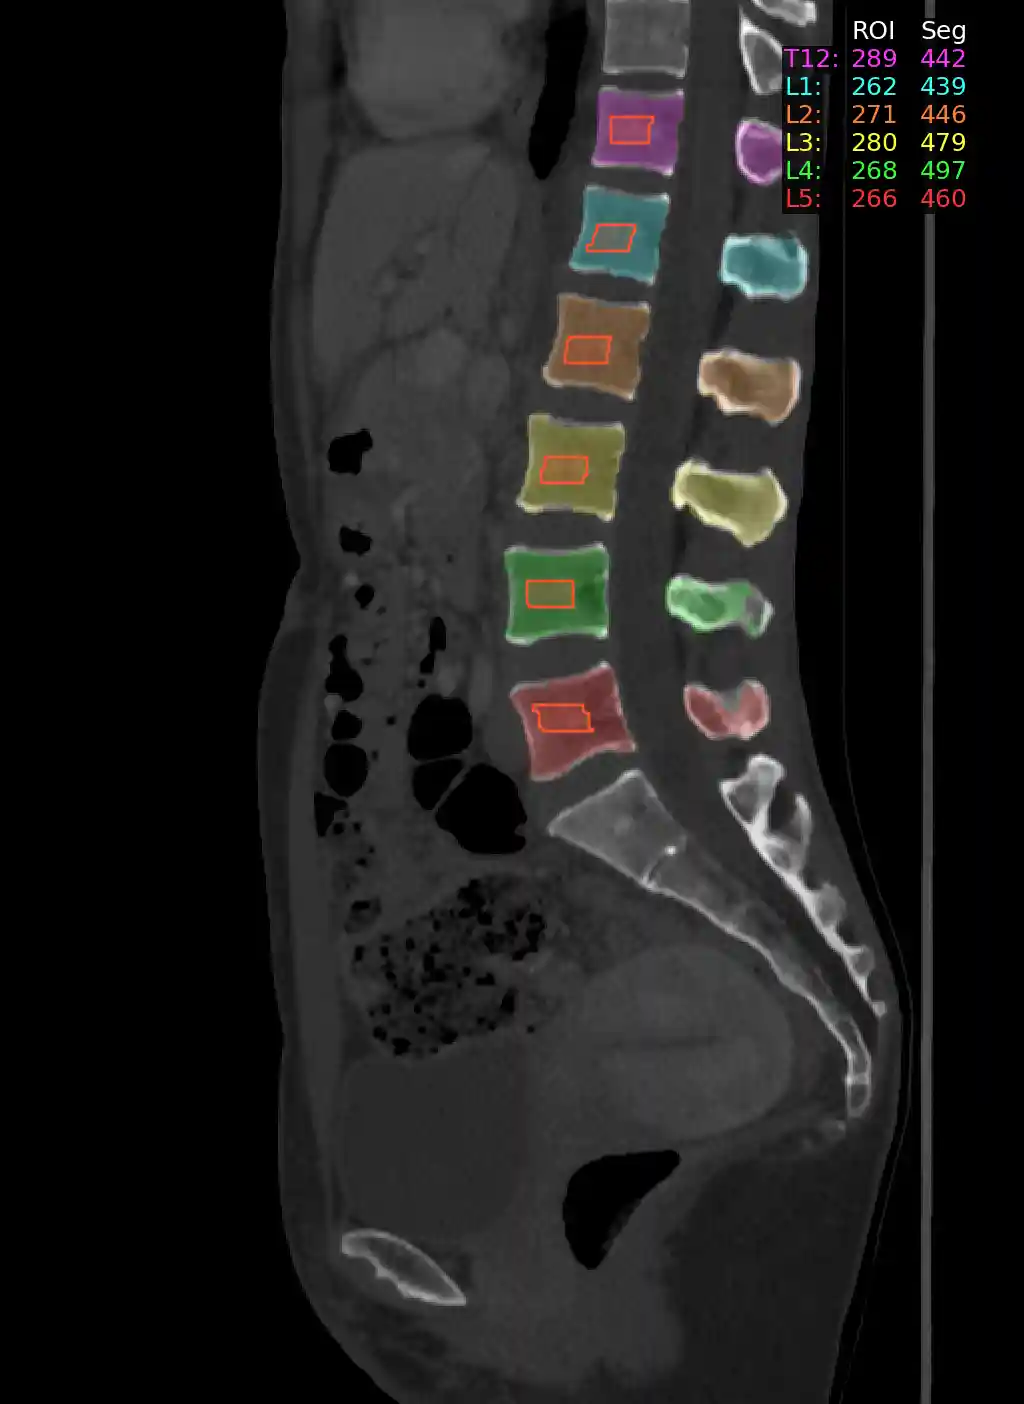

Spine Bone Mineral Density from 3D Trabecular Bone Regions at T12-L5

Example Output Image